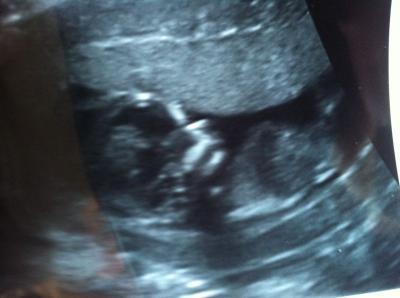

Bild vom Krümel

ist dieses Mal leider nicht sooo gut geworden. Das Model wollte einfach nicht still halten...

doch ich finde das voll schön!! man sieht schon gut eine nase und den mund! super!!